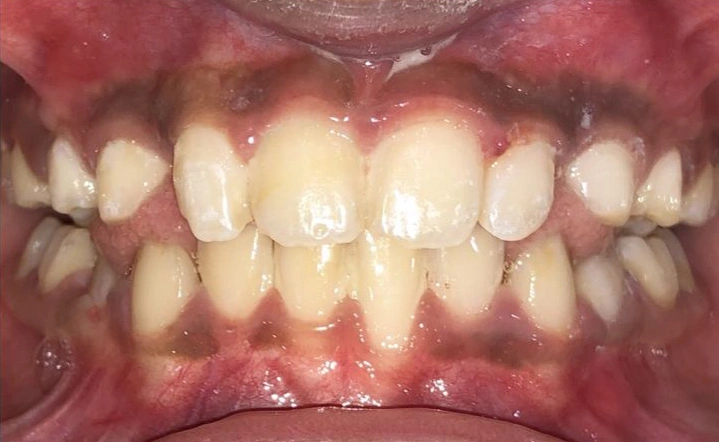

2. The Underbite: When the Upper Teeth Are Behind the Lower Teeth

Another common issue is an underbite. This is a horizontal problem where the lower teeth are pushed out past the upper teeth.

It can lead to functional problems and damage if not addressed early.

Visual Example:

Example #1 (young adult):

Example #2 (young adult):